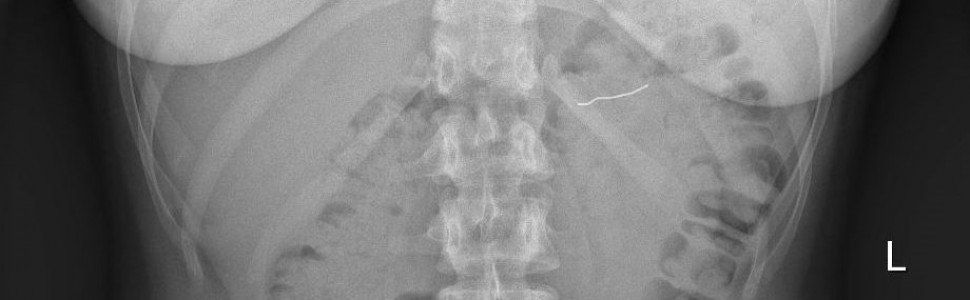

Połknięcie ciała obcego jest jednym z powikłań występujących podczas wykonywania procedur stomatologicznych. W leczeniu ortodontycznym istotne ryzyko stwarzają aparaty montowane na stałe w jamie ustnej, które w wyniku awarii mogą w całości lub w części przedostać się do dróg oddechowych lub pokarmowych pacjenta. W artykule opisano przypadek przedostania się fragmentu aparatu ortodontycznego do dróg pokarmowych podczas spożywania posiłku. Przedstawiono postępowanie w przypadku połknięcia ciała obcego, możliwe komplikacje oraz środki bezpieczeństwa możliwe do zastosowania podczas leczenia ortodontycznego z wykorzystaniem aparatów grubołukowych.

Foreign-body ingestion is one of the complications that occur during dental procedures. In orthodontic treatment, a significant risk is posed by fixed braces that, as a result of failure, can fully or partially enter the patient’s respiratory or digestive tract. This article describes a case in which part of an orthodontic appliance entered the digestive tract while eating a meal. This paper presents how to proceed when a foreign body is ingested, possible complications and safety measures during orthodontic treatment with wide-arch appliances.